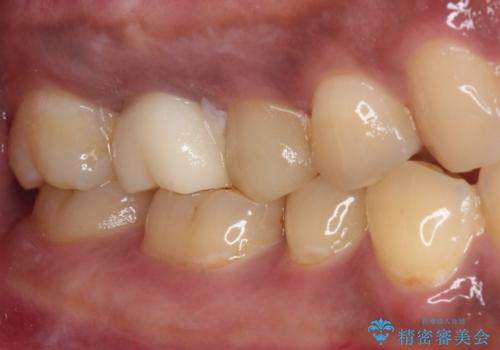

不快感の強い奥歯 オールセラミッククラウンでのむし歯治療

- とにかく奥歯に不快感を感じるとのことで来院された患者様です。

神経近くにまで及んでいる大きなむし歯や、歯肉の中深く、骨の近くにまでむし歯が進行している歯など、問題の多い状態でした。

神経を温存するための処置や、歯肉深くにまで及んだむし歯を改善するための歯周外科処置などを行っていき、オールセラミッククラウンにて補綴治療を行うこととしました。